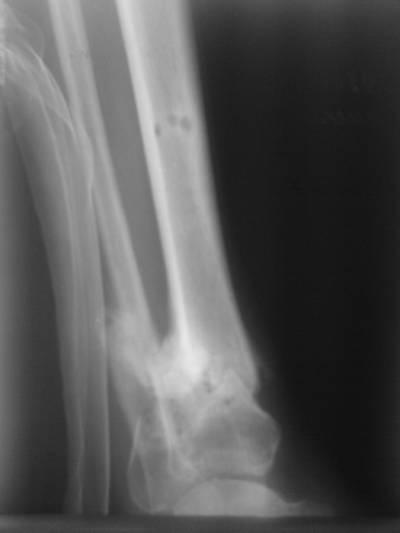

Больной случайно попал в поле зрения с переломом шейки бедра. Страдает

хр. алкоголизмом. От когда-то предложенного удлиннения голени пациент

отказался. После снятия аппарата он пропал как с белых яблонь дым ...

Укорочение конечности 3 см. Передвигался без дополнительной опоры с

"нарощенной" подошвой на правой обуви. Ограничение тыльного и

подошвенного сгибания - умеренные (всего примерно 50%, не измерял).

----------- следущая часть -----------

Вложение не в текстовом формате было извлечено…

Имя     : Tibi2.jpg

Тип     : image/jpeg

Размер  : 36109 байтов

Описание: отсутствует

Url     : http://weborto.net:8080/pipermail/ortho/attachments/20070606/3107b3f1/attachment-0007.jpg